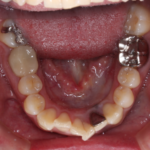

【叢生】インビザライン症例:ガタガタが気になる

治療前 治療後 症例の詳細 主訴 ガタガタが気になる ...